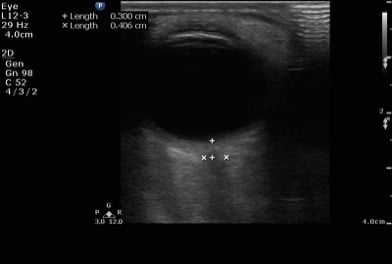

Figure 1. Sonographic eye anatomy

- Because the ocular chamber is fluid-filled, under ultrasound, it will appear as a round, anechoic structure.

- The most anterior structure seen, after the layer of ultrasound gel, is the eyelid.

- Just deep to the eyelid is the cornea and the anterior chamber. If too much pressure is applied during the ocular ultrasound examination, the anterior chamber may become compressed. It is important to avoid applying direct pressure to the eyelid.

- If the patient attempts to look down during the exam, you may be able to visualize the iris and pupil.

- The lens appears as a hyperechoic, curved line, located deep to the iris. If the patient has undergone cataract surgery, you may see two thin, hyperechoic parallel lines instead of the concave hyperechoic line.

- Normal vitreous humor will appear anechoic.

- The vitreous, retina, and choroid are located along the inside of the globe. Normally, you cannot differentiate one from the other.

- The most far field identifiable structure is the optic nerve. The parallel hyperechoic lines are the optic nerve sheath, since the optic nerve is hypoechoic and nondistinctive.

- Figure 3. Ultrasound image of a normal eye.